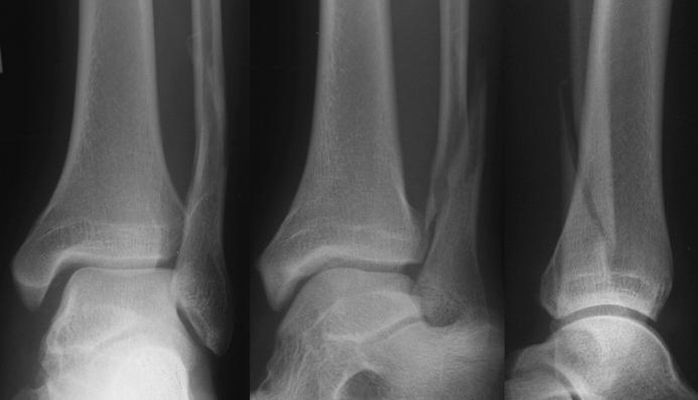

骨折圖片